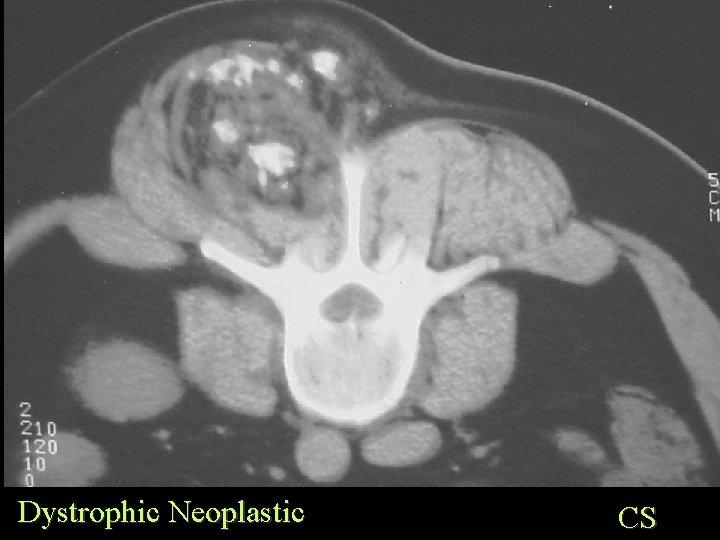

Soft Tissue Calcification By Cause Dystrophic Calcification Neoplastic • Synovial sarcoma • Liposarcoma • Any less commonly

Dystrophic Neoplastic SS

Dystrophic Neoplastic CS